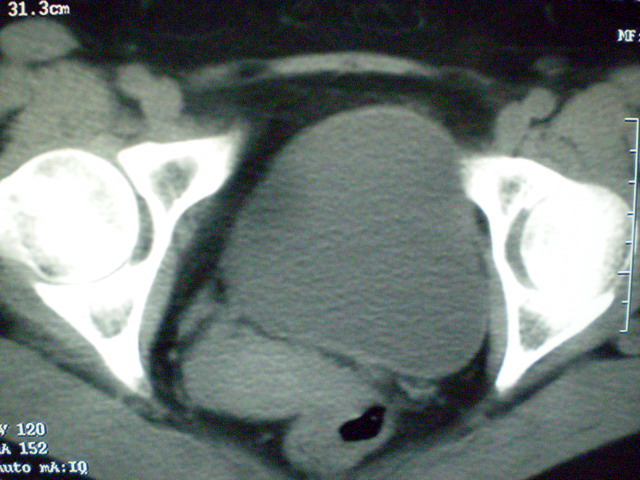

f 60y,b超提示脂肪瘤.[img][/img]

右侧附件囊性畸胎瘤,三种组织均见.

右侧附件囊性畸胎瘤.

那个高密度灶形状好象牙齿。典型,收藏了

脂肪密度肿块,内可见团块状影,典型皮样囊肿

的确比较典型的畸胎瘤!不过,应该确切的说是盆腔畸胎瘤,右侧附件来源的可能性比较大。